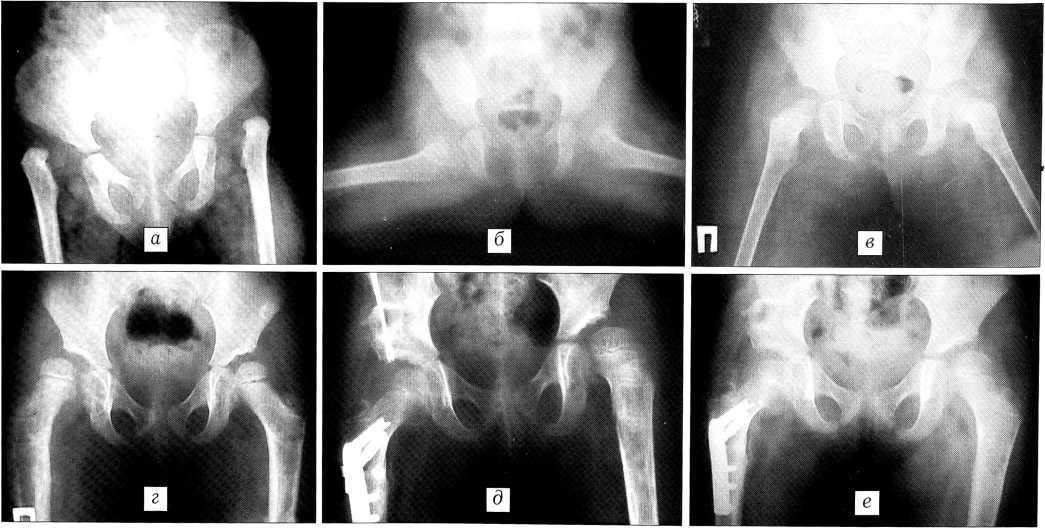

Больная X.,2,5 лет. Диагноз: врожденный вывих бедер. Диагноз впервые установлен в возрасте 2,5 лет. До обращения в ЦИТО лечения не получала. При поступлении: высокий двусторонний вывих бедер (рис. 2, а). Первым этапом наложена система скелетного вытяжения по методике «over head» (рис. 2, б). Далее произведено закрытое вправление вывихов с иммобилизацией в кокситной гипсовой повязке. По снятии гипса головки обоих бедер располагаются во впадинах (рис. 2, в). Проведен курс восстановительного лечения. Нагрузка на конечности разрешена через 1 год после устранения вывихов. Однако с ростом ребенка сформировались остаточные подвывихи бедер (рис. 2, г). В связи с этим была произведена укорачивающая деторсионно-варизирующая остеотомия правого бедра с остеотомией таза по Солтеру справа (рис. 2, д). В настоящее время головка правого бедра центрирована во впадине, покрытие полное (рис. 2, е). Аналогичное вмешательство планируется на левом тазобедренном суставе.

Рис. 2. Больная X. 2,5 лет. Диагноз: врожденный вывих бедер.

а - рентгенограмма при поступлении; б —в процессе лечения по методике «over head»; в — после закрытого вправления и гипсовой иммобилизации; г — остаточные подвывихи бедер: коэффициент покрытия головки справа 0,4, слева — 0,7, угол патологической антеторсии справа 65°, слева 60°, угол Виберга справа — 10°, слева 5°, угол вертикального соответствия справа 60°, слева 75°; д — произведены остеотомия таза по Солтеру и деторсионно-варизирующая остеотомия бедра справа; е — через 4 мес после операции: коэффициент покрытия головки справа 1, угол Виберга 35°, угол вертикального соответствия 90°.

Больной А., диагноз: врожденный вывих левого бедра. Впервые вывих выявлен в ЦИТО в возрасте 4 лет (рис. 4, а). Сначала больному произведена деторсионно- варизирующая остеотомия левой бедренной кости с фиксацией пластиной и одновременно наложена дистракционная система (рис. 4, б). В послеоперационном периоде головка бедра низведена до уровня нижнего края вертлужной впадины и выполнено закрытое вправление ее. Проводились курсы консервативного лечения. Через 1 год разрешена нагрузка на ногу. На контрольных рентгенограммах головка левого бедра центрирована во впадине (рис. 4, в). В процессе роста у больного сформировался дефицит покрытия головки левой бедренной кости (рис. 4, г), в связи с чем в возрасте 8 лет выполнена ацетабулопластика по Пембертону слева (рис. 4, д). Через 2 года после операции клинико-рентгенологический результат хороший (рис. 4, е).

Рис. 4. Больной А. 4 лет. Диагноз: врожденный вывих левого бедра.

а рентгенограмма при поступлении; б — произведена деторсионно-варизирующая остеотомия левого бедра, наложена дистракционная система; в — через 1 год после вправления: сустав стабилен, коэффициент покрытия головки 1; г — рентгенограммы в возрасте 8 лет: остаточный подвывих левого бедра, коэффициент покрытия головки 0,6, ацетабулярный индекс 35°, угол Виберга 5°; д — ацетабулопластика по Пембертону слева; е — функциональный и рентгенологический результат через 2 года после операции: объем движений в тазобедренных суставах полный, симптом Тренделенбурга отрицательный с обеих сторон, слева ацетабулярный индекс 10°, угол Виберга 35°, коэффициент покрытия головки 1.